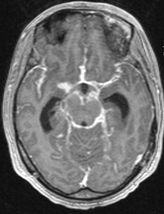

A 26-year-old man was admitted in our Rehabilitation Unit in May 2022 after being diagnosed with TBM. The patient presented to the emergency department with a 2-week history of fever, disorientation, decreased lower limbs strength and urinary incontinence. He had a recent history of contact with tuberculosis (TB), with a positive interferon gamma release assay test. Brain magnetic resonance imaging (MRI) with gadolinium contrast revealed hydrocephalus and diffuse leptomeningeal enhancement with basal cistern involvement (Figure 1). Acute ischemic brain lesions with hemorrhagic transformation in the right globus pallidus and anterior limb of internal capsule consistent with infarctions due to infectious arteritis, were also noted (Figures 2 & 3). Spine MRI with gadolinium contrast revealed diffuse cervical, thoracic, lumbar and sacral enhancement of meninges overlying the spinal cord and cauda equina nerve roots (Figure 4). These images were suggestive of TB infection. Blood cultures, serologies and cerebrospinal fluid (CSF) culture were negative for TB bacilli and he had no relevant medical history, including risk factors for being immunocompromised. Nevertheless, presumptive diagnosis of TBM was made in the setting of relevant clinical and epidemiologic factors in combination with typical CSF and MRI findings.

Figure 1 Brain MRI T1 with gadolinium contrast images, axial view - diffuse leptomeningeal enhancement with basal cistern involvement.